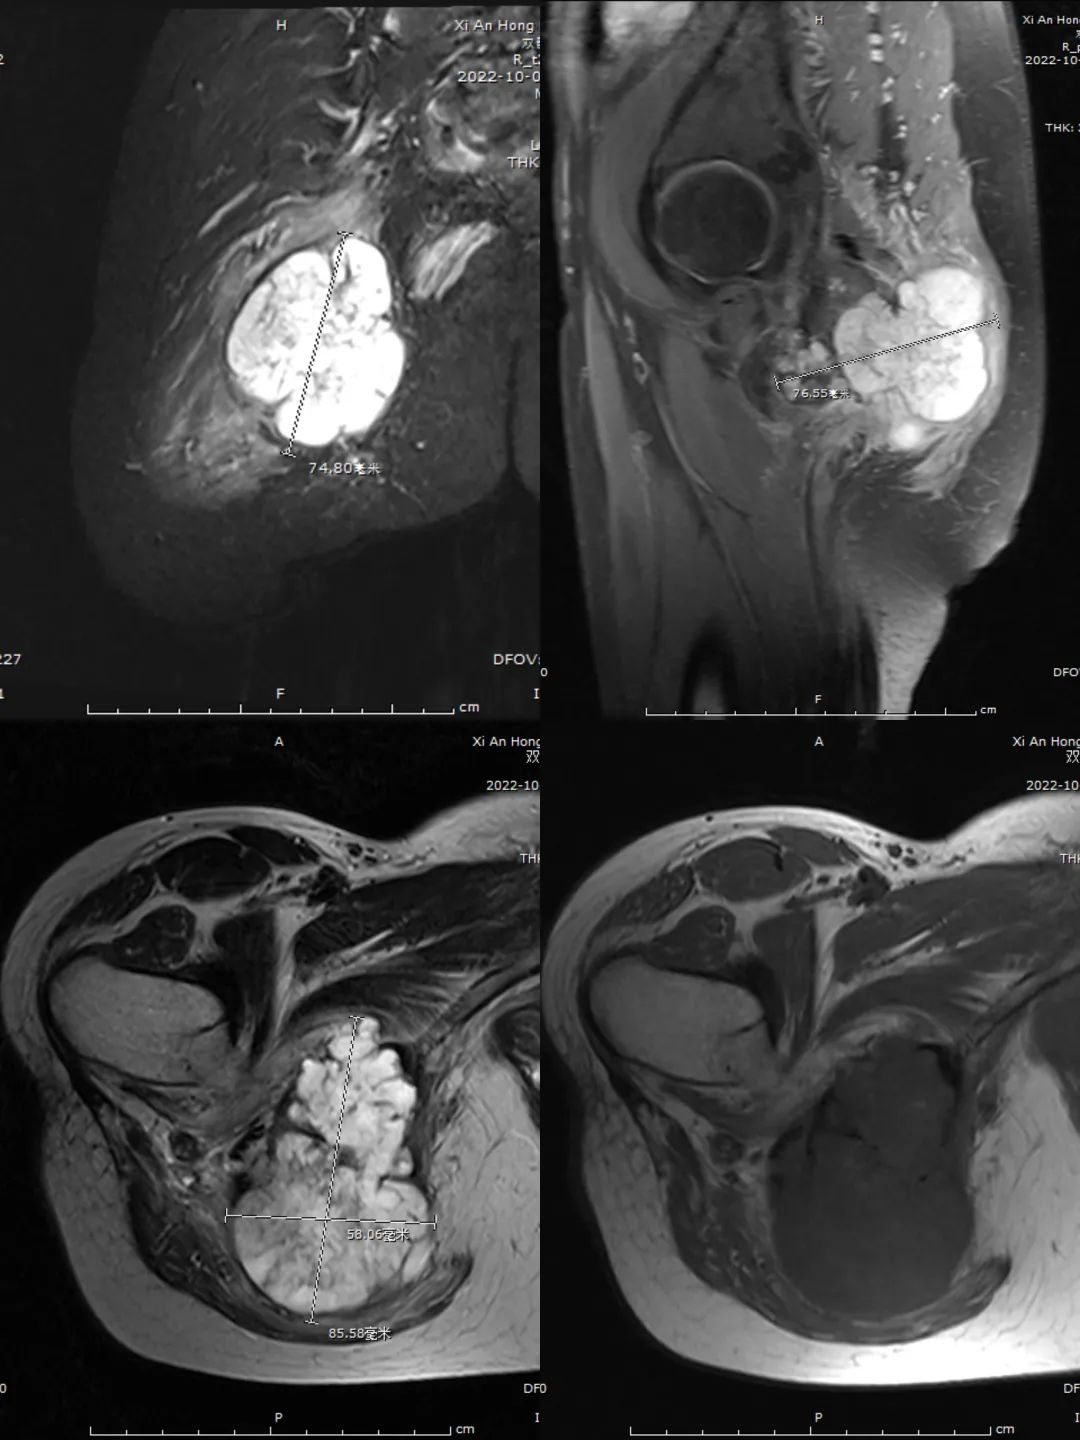

42岁女子小王(化名)因右侧臀部出现疼痛,伴功能障碍半年多,来到西安市红会医院就诊,完善CT及MR检查发现,右侧坐骨巨大肿瘤,肿瘤后侧缘紧紧压迫坐骨神经、盆腔血管;内侧缘及前缘临近直肠、阴 道、尿道等盆腔内脏器仅6-9mm。患者接受病灶穿刺活检,病理结果显示为右侧坐骨软骨肉瘤2级。

(术前核磁共振显示骨盆肿瘤)